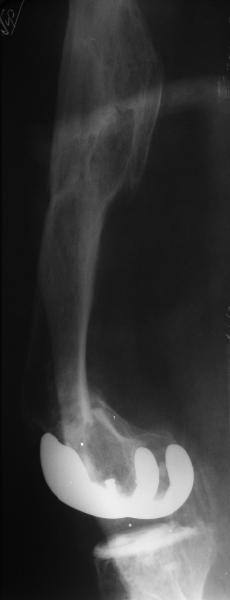

Глубокоуважаемые коллеги, Мужчина 41 года поступил с повторным (предыдущий в 2001 г.) переломом (3-недельной давности) над протезом коленного сустава.

В 1994 множественная травма, в том числе открытый перелом надколенника, осложнившийся гнойным артритом, и на этой же стороне перелом диафиза бедра (лечили в аппарате). В 1998 г. выполнено эндопротезирование коленного сустава. Предыдущий перелом (3 года назад) лечили консервативно, сросся при неустраненном смещении дистального блока бедра кзади ~ на 1 см. Амплитуда движений в коленном суставе перед последним переломом была ~90 градусов. Ходил без дополнительной опоры. Снимки в приложении. Какие будут предложения по поводу оперативного лечения в нынешней ситуации? У нас споры между ретро- и антеградным закрытым интрамедуллярным остеосинтезом.

A male 41 years old transferred to our unit with 3 week old femoral fracture near the knee prosthesis after a mimimal fall. In 1994 he sustained multiple injury with open patella fracture (complicated with septic arthritis), and ipsilateral femoral shaft fracture treated by ex-fix. TKA performed in 1998. In 2001 he got a periprosthetic fracture which was treated nonoperatively and healed with ~1 cm dorsal displacement of the distal femoral block. Knee ROM prior the recent injury was about 90-95 degrees. He didn't use walking aid. Images attached. I request your suggestions regarding surgical options in the situation? We mostly discuss ante- vs retrograde closed nailing.